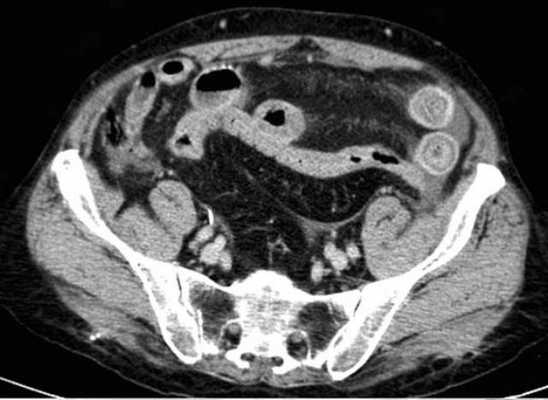

(а) При КТ с контрастированием в аксиальной проекции выявлена транспозиция верхней брыжеечной артерии (указатель) и вены (стрелка).

(б, в) На более низких уровнях при КТ в аксиальной проекции выявлен симптом «водоворота» (стрелка), представляющий собой перекручивание верхней брыжеечной вены и ее ветвей, брыжеечного жира и петель кишки вокруг верхней брыжеечной артерии по часовой стрелке.